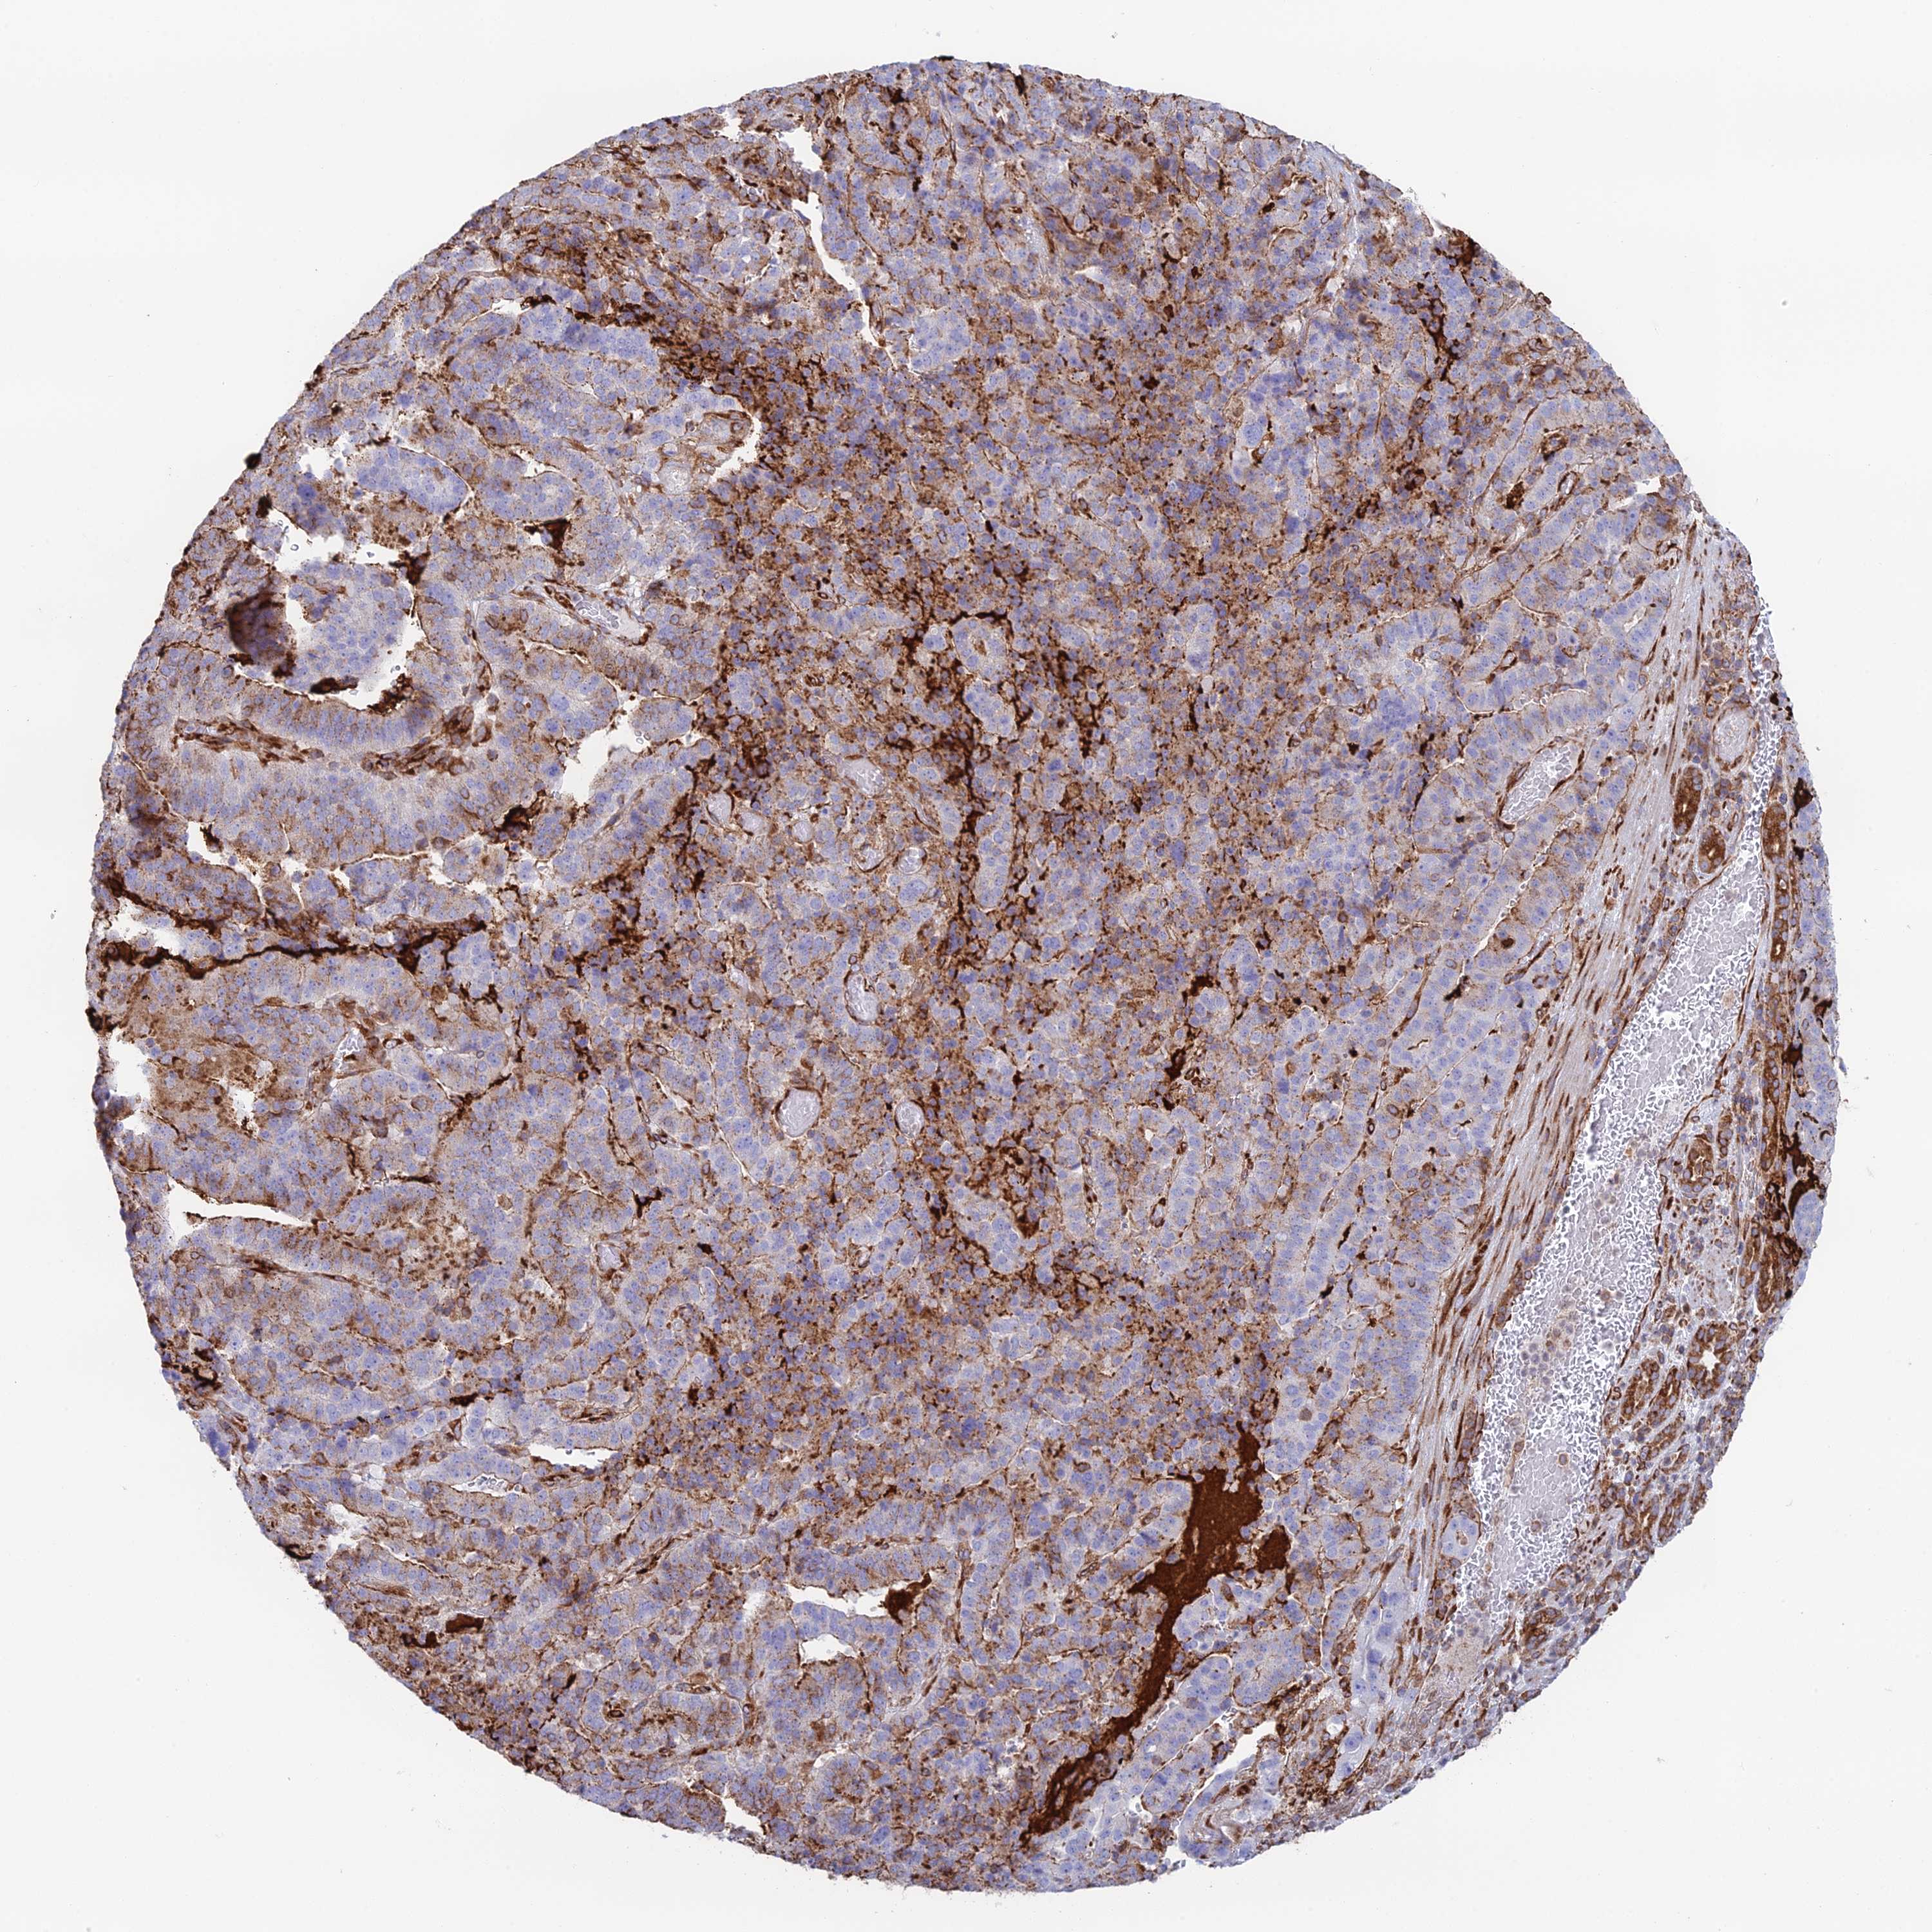

STOMACH CANCER - Protein expressioni

A mouse-over function shows sample information and annotation data. Click on an image to view it in a full screen mode. Samples can be filtered based on level of antibody staining by selecting one or several of the following categories: high, medium, low and not detected. The assay and annotation is described here.

Antibody stainingi

Antibody staining in the annotated cell types in the current human tissue is reported as not detected, low, medium, or high, based on conventional immunohistochemistry profiling in selected tissues. This score is based on the combination of the staining intensity and fraction of stained cells.

Each image is clickable and will lead to virtual microscopy that enables deeper exploration of all samples and also displays staining intensity scores, fraction scores and subcellular localization as well as patient and tissue information for each sample.

Antibody HPA043648

Staining

High

Medium

Low

Not detected

Intensity

Strong

Moderate

Weak

Negative

Quantity

>75%

75%-25%

<25%

None

Location

Nuclear

Cytoplasmic/membranous

Cytoplasmic/membranous,nuclear

Adenocarcinoma, NOS